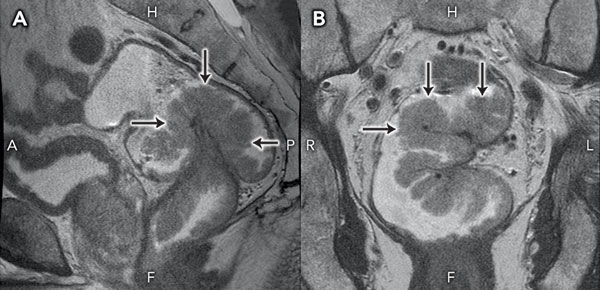

Staging magnetic resonance imaging of the pelvis performed on the day of discharge clearly demonstrated a large, sessile tumour arising from the left rectal wall (Box 3). Appearances were thought to be consistent with a T2 lesion. After 3 weeks of outpatient convalescence, the patient returned for elective low anterior resection, which revealed a large, exophytic lesion within the rectum (Box 4). Histopathological examination of the resected specimen (Box 5) confirmed hypersecretory tubulovillous adenoma with low-grade dysplasia.

3 Sagittal (A) and coronal (B) magnetic resonance images of the causative lesion

H = head. F = feet. A = anterior. P = posterior. R = right. L = left. |